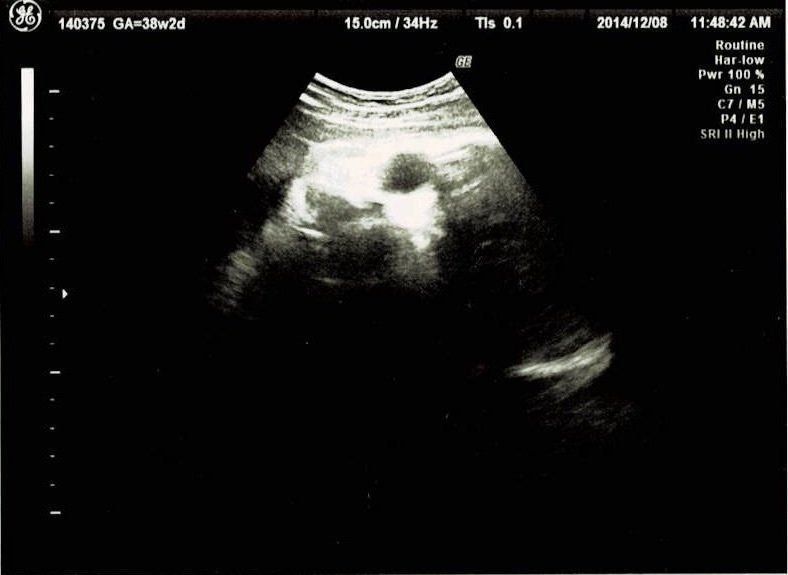

妊娠38週目エコー写真 出産直前! マイナートラブル頻発

いよいよ生まれそうです。この頃は、急に陰部のかゆみが出たり、陣痛のような痛みがずっと続いたりと、体の変化で毎日気を張っていました。陣痛のような痛みをアプリで計測し、結果を印刷して先生に見せたところ、もうお産が始まっていても良い間隔だと言われました。それでも動きが弱すぎて、実際に生まれるまでさらに一週間かかりました。